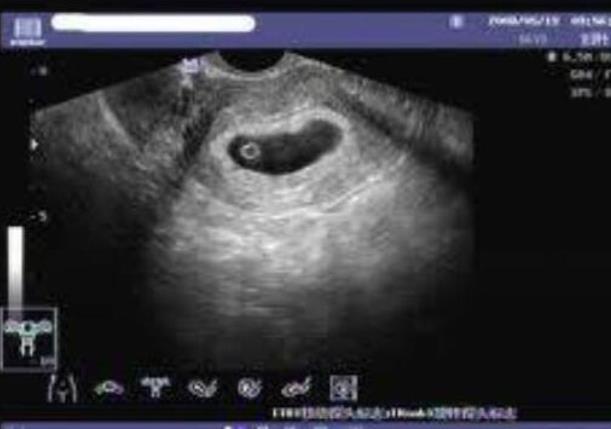

安徽供卵试管 2023在安徽省立医院做供精试管需要满足什么条件? ‘孕囊形状看男女在孕多少天比较准’